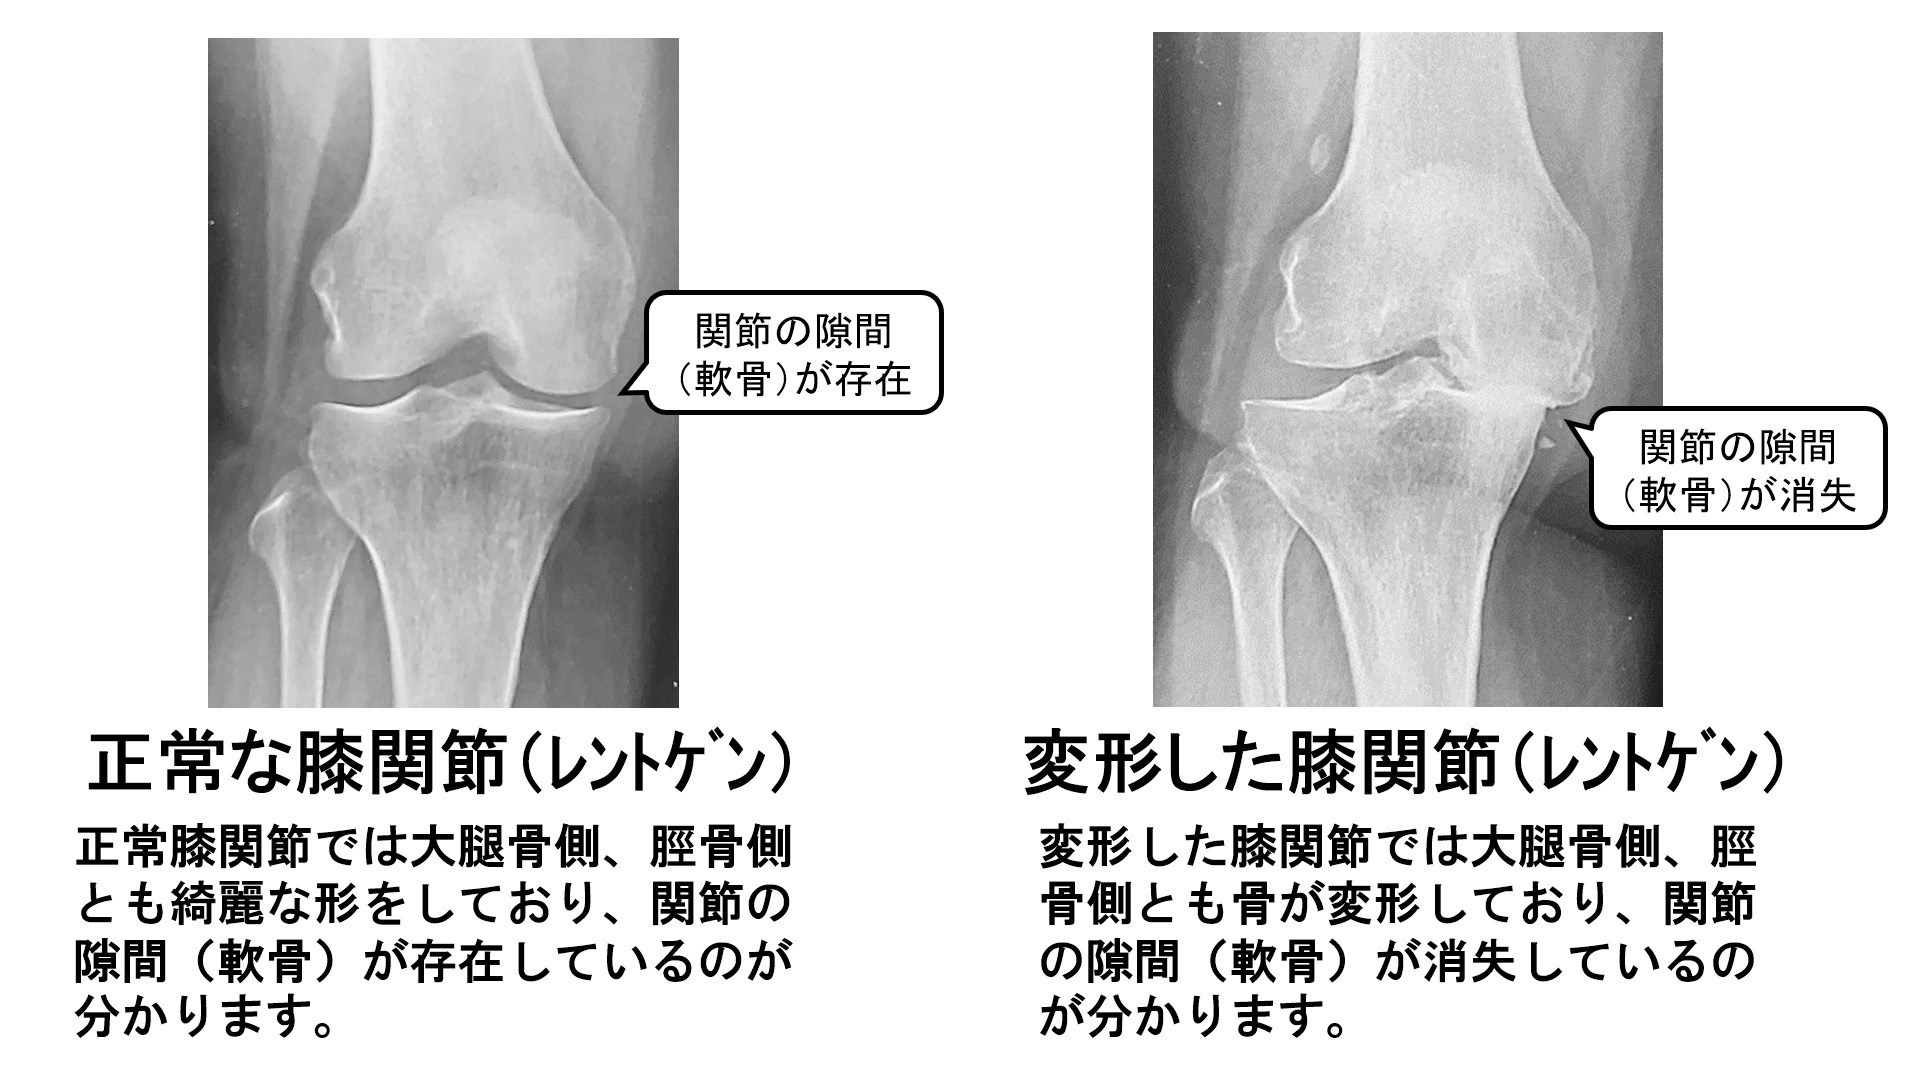

膝関節は大腿骨、脛骨(すねの骨)などの骨があわさってできています。

これらの関節表面は「軟骨」に覆われており、衝撃を緩和するクッションのような役割を果たしています。しかし年齢を重ねると「軟骨」はすり減って痛んできます(一般に軟骨の寿命は60年といわれています)。すると骨どうしがじかに接するようになり、痛みや変形が生じるのです(下図、正常関節と変形性股関節症と変形性膝関節症のイメージ、レントゲン)。